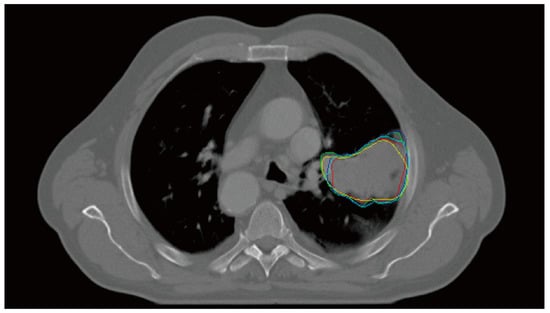

Interobserver Variability Prediction of Primary Gross Tumor in a Patient with Non-Small Cell Lung Cancer

2.1. Multiple Delineation Database

2.2. IOV Map: Ground Truth

3.2. Analysis of the Effect of the IOV Map on the Reduction of IOV in Clinics